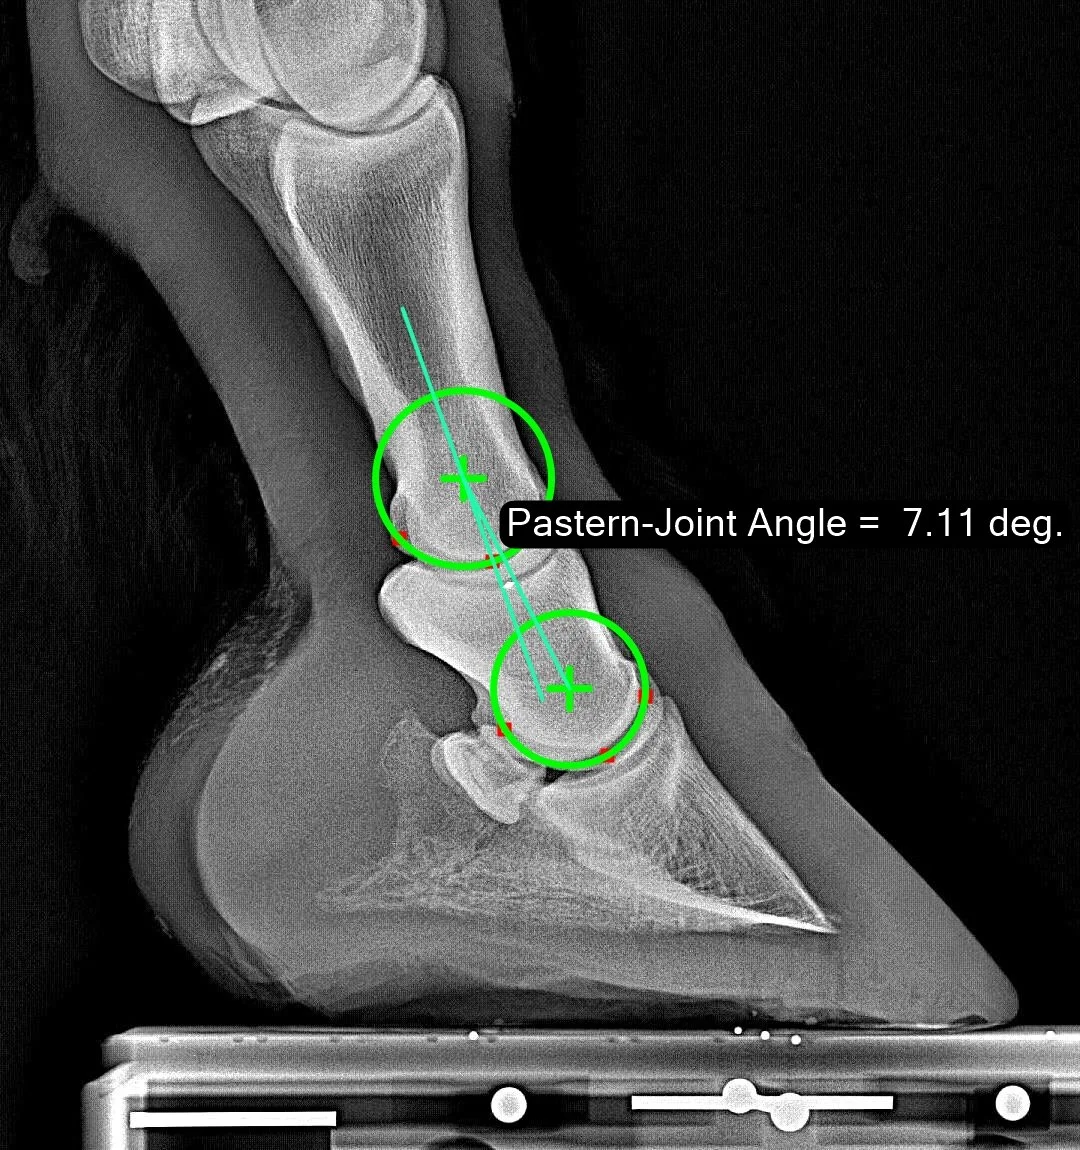

Pastern-Joint Angle

The Pastern-Joint Angle measures the angulation between the P1 and P2 bones. To be precise, it is measured as follows: construct a line connecting the rotation centers of the pastern and coffin joints. Then measure the angular difference between the centerline of the P1 bone and that line. The details are discussed in this publication. To repeatably quantify a given leg/hoof, it is important to stand the horse with cannon bone approximately vertical when imaging.

Normal Range

The observed normal range is from 0 degrees to 8.9 degrees with a median of 4.5 degrees. The larger the value, the more ‘upright’ the pastern. At 7.1 degrees, this sample shows a somewhat more upright (or ‘broken-back’) pastern joint angle than average, but still within our 70%-of-all-horses normality zone.